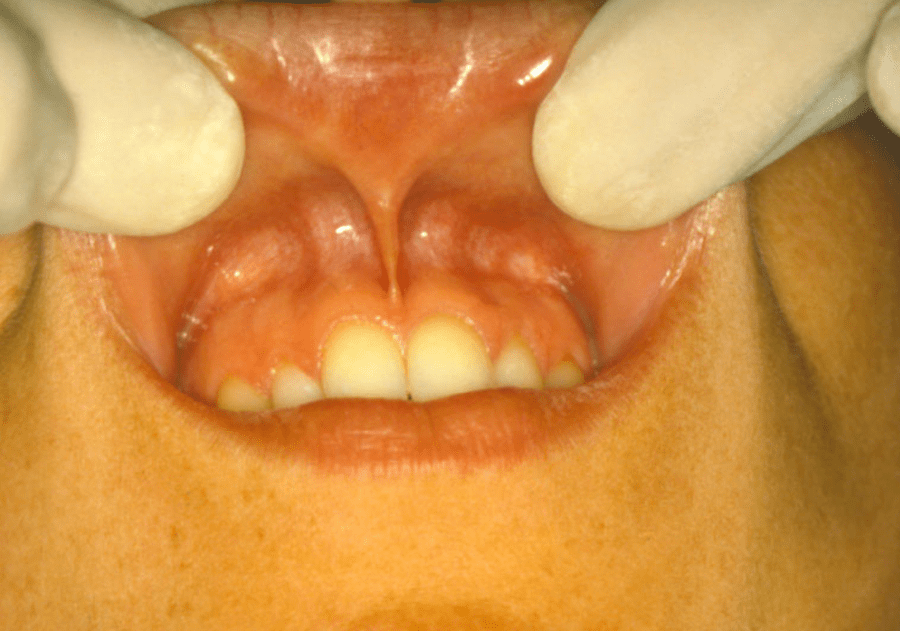

L’esame intra-orale prende in considerazione la lingua, le mucose, il parodonto, la dentatura presente e l’occlusione del paziente. Si divide quindi in parodontale, dentale ed occlusale.